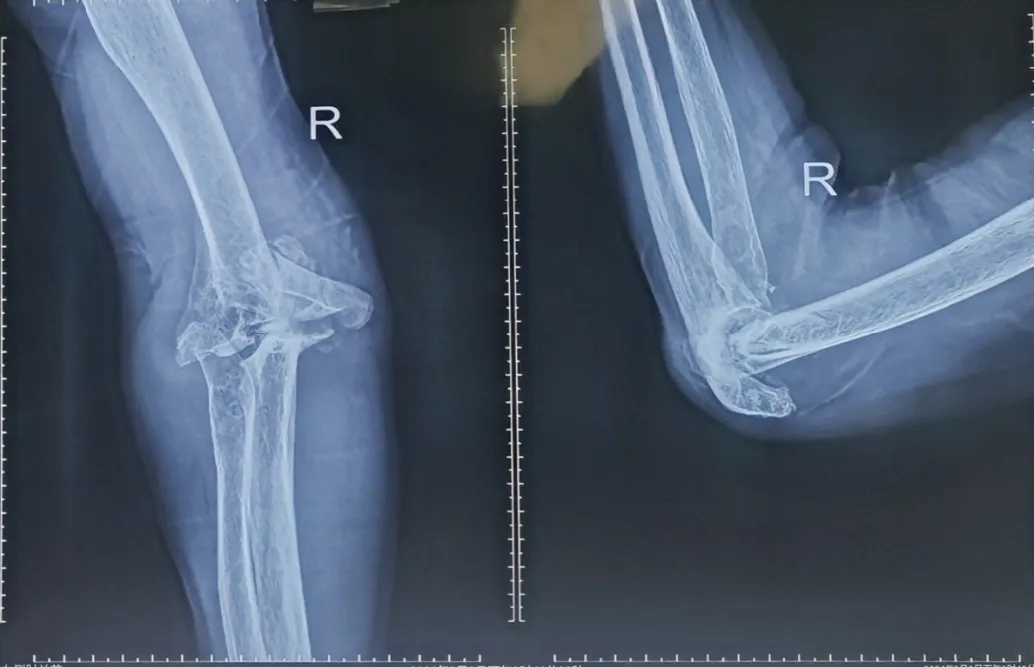

为深入推动医院高质量发展及京蒙协作临床重点专科建设项目落地见效,进一步推动创伤外科学科建设持续发展,近日,91直播 客座教授、北京积水潭医院李庭教授受邀来91直播 会诊并指导手术。李庭教授高度重视91直播 创伤急救外科学科建设工作,为91直播 创伤外科中心A区一位右肱骨髁间骨折、右上尺桡关节脱位、右肘关节粉碎性骨折并患有严重基础病的患者进行会诊并指导手术。

患者孙某,65岁,患者于家中不慎摔伤右上臂,患者为求进一步诊治来91直播 就诊,被诊断为:右肱骨髁间骨折、右上尺桡关节脱位、肝血管瘤、单纯性肾囊肿。另外,患者有类风湿病史38年。手术治疗的目的是尽最大限度恢复肘关节的功能。